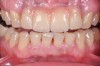

Fig 5. Preoperative view of patient requiring esthetic changes up to at least the bicuspids.

Figure 5

Fig 6. Postoperative view with CL-I feldspathic porcelain veneers up to the first bicuspid.

Figure 6